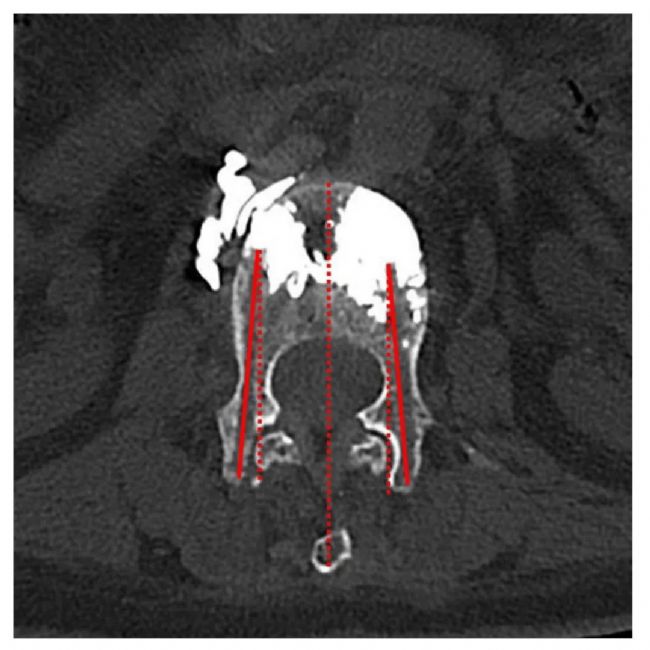

❐ 數(shù)據(jù)收集:收集了OVCF患者的基線特征,包括年齡、性別、BMDT值和椎體骨折部位。從術(shù)前、術(shù)后和術(shù)后3個月隨訪的腰椎正側(cè)位片上判斷骨水泥的彌散程度。手術(shù)過程中,記錄使用C形臂的透視次數(shù)、總輻射劑量以及是否存在骨水泥滲漏。使用VAS疼痛評分評估患者椎體骨折后的疼痛,使用ODI評分評估患者的恢復(fù)和康復(fù)情況。記錄了術(shù)前、術(shù)后3天和術(shù)后3個月的VAS和ODI評分。根據(jù)術(shù)后隨訪CT掃描中患者病椎的橫截面測量并記錄了穿針的外展角度。

① 根據(jù)術(shù)后隨訪CT的橫截面測量穿刺外展角,兩組之間存在顯著性差異(P<0.05)。